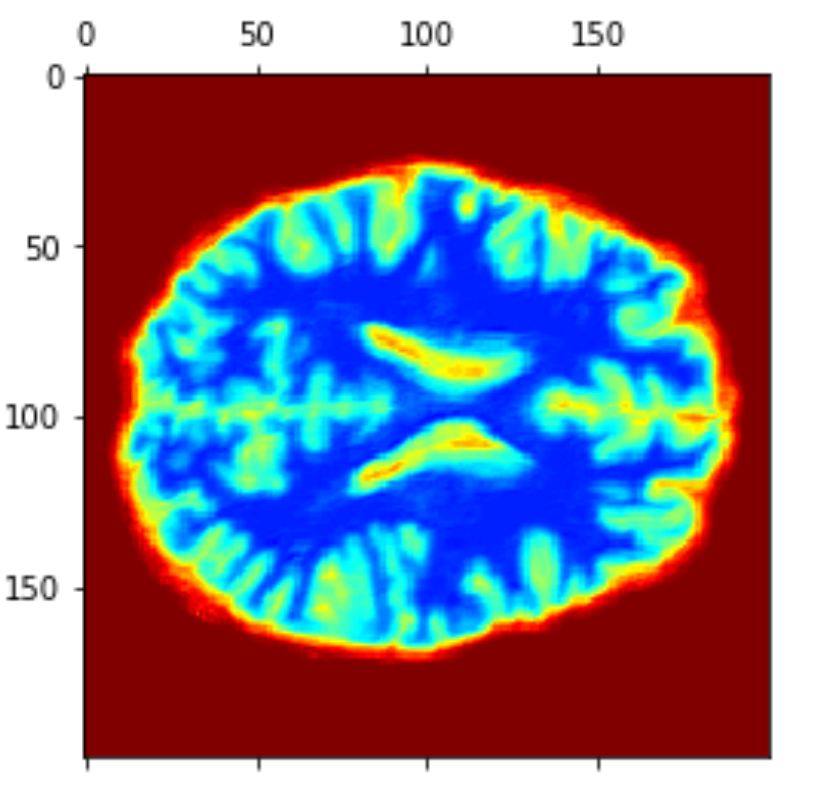

PCA reconstruction

Eigen brains

Eigen brains.

First four eigenbrains (components 0 to 3) of the PET ADNI dataset. (Functional Brain Imaging Synthesis Based on Image Decomposition and Kernel Modeling: Application to Neurodegenerative Diseases)

Applying PCA

1113x125000

125000x1113

125000x809

Transpose

PCA(99.9)

Reshaping

Reshape

50x50x50

eigen brain 809

eigen brain 1

Plotting

0.417

0.069

0.035

0.022

1

2

3

4

Average brains